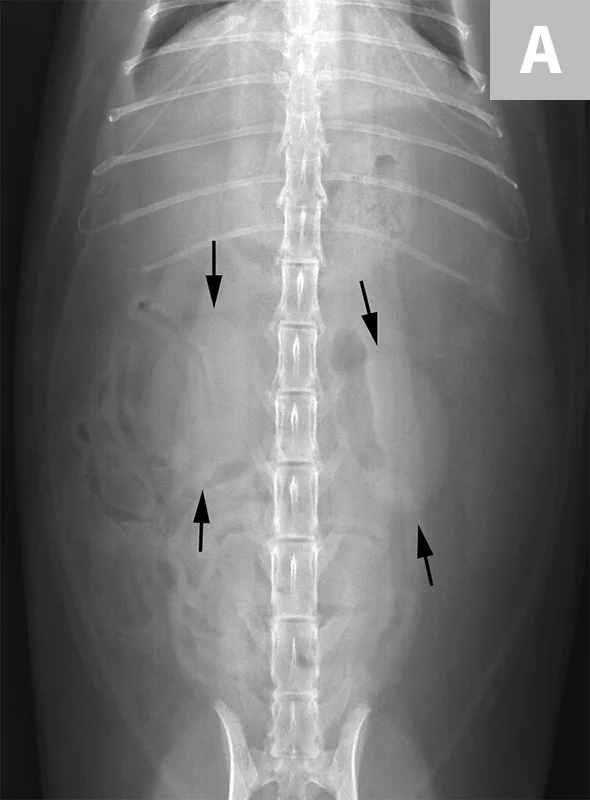

FIGURE 5A

Lateral abdominal radiograph of a dog with 2 well-defined, oval mineral opacities superimposed over the retroperitoneal space caudal and dorsal to the kidneys (arrows). Based on the ventrodorsal projection (not shown), these calculi were likely to be associated with the right ureter.